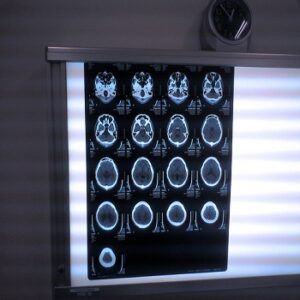

A radiologist is a specialist whose primary role in a patient’s care is to administer and read diagnostic scans like CT’s, MRI’s and X-Rays.

Their advice is usually sought to help interpret these scans so that the attending physician can make a diagnosis and begin a plan of treatment. An interventional radiologist is able to do all of that, but has also extended his studies so that he may help treat a condition with minimally invasive surgery using imagery as his guide. Many of these procedures are high risk and errors could lead to serious complications. If you were injured during an image guided procedure you should speak with a Missouri medical malpractice attorney. If the radiologist who performed the procedure did not follow medical protocol you could be eligible to receive compensation for your injury.